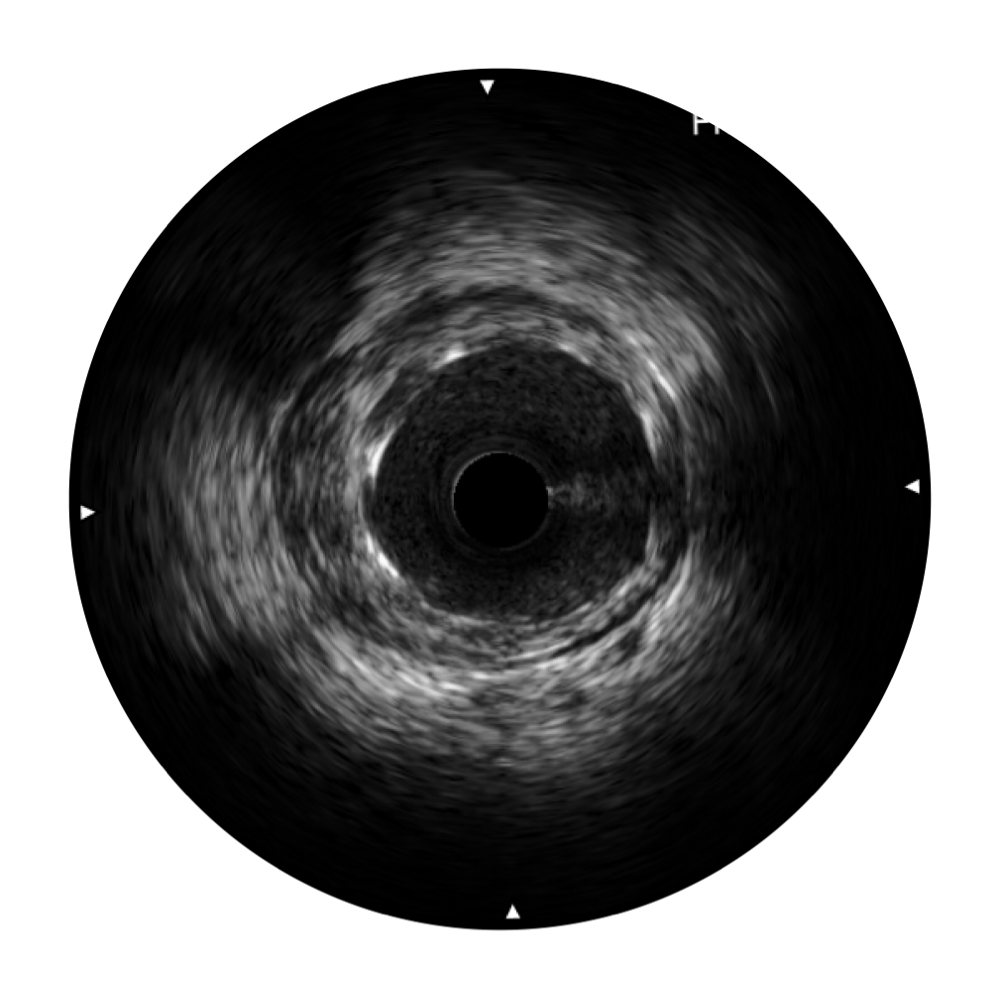

传统IVUS图像

对比传统IVUS导管成像,乐玩lewin国际宽频IVUS图像的近场支架梁显影更细腻,远场中膜外血管仍清晰可辨,兼顾远中近,兼顾分辨力与穿透深度